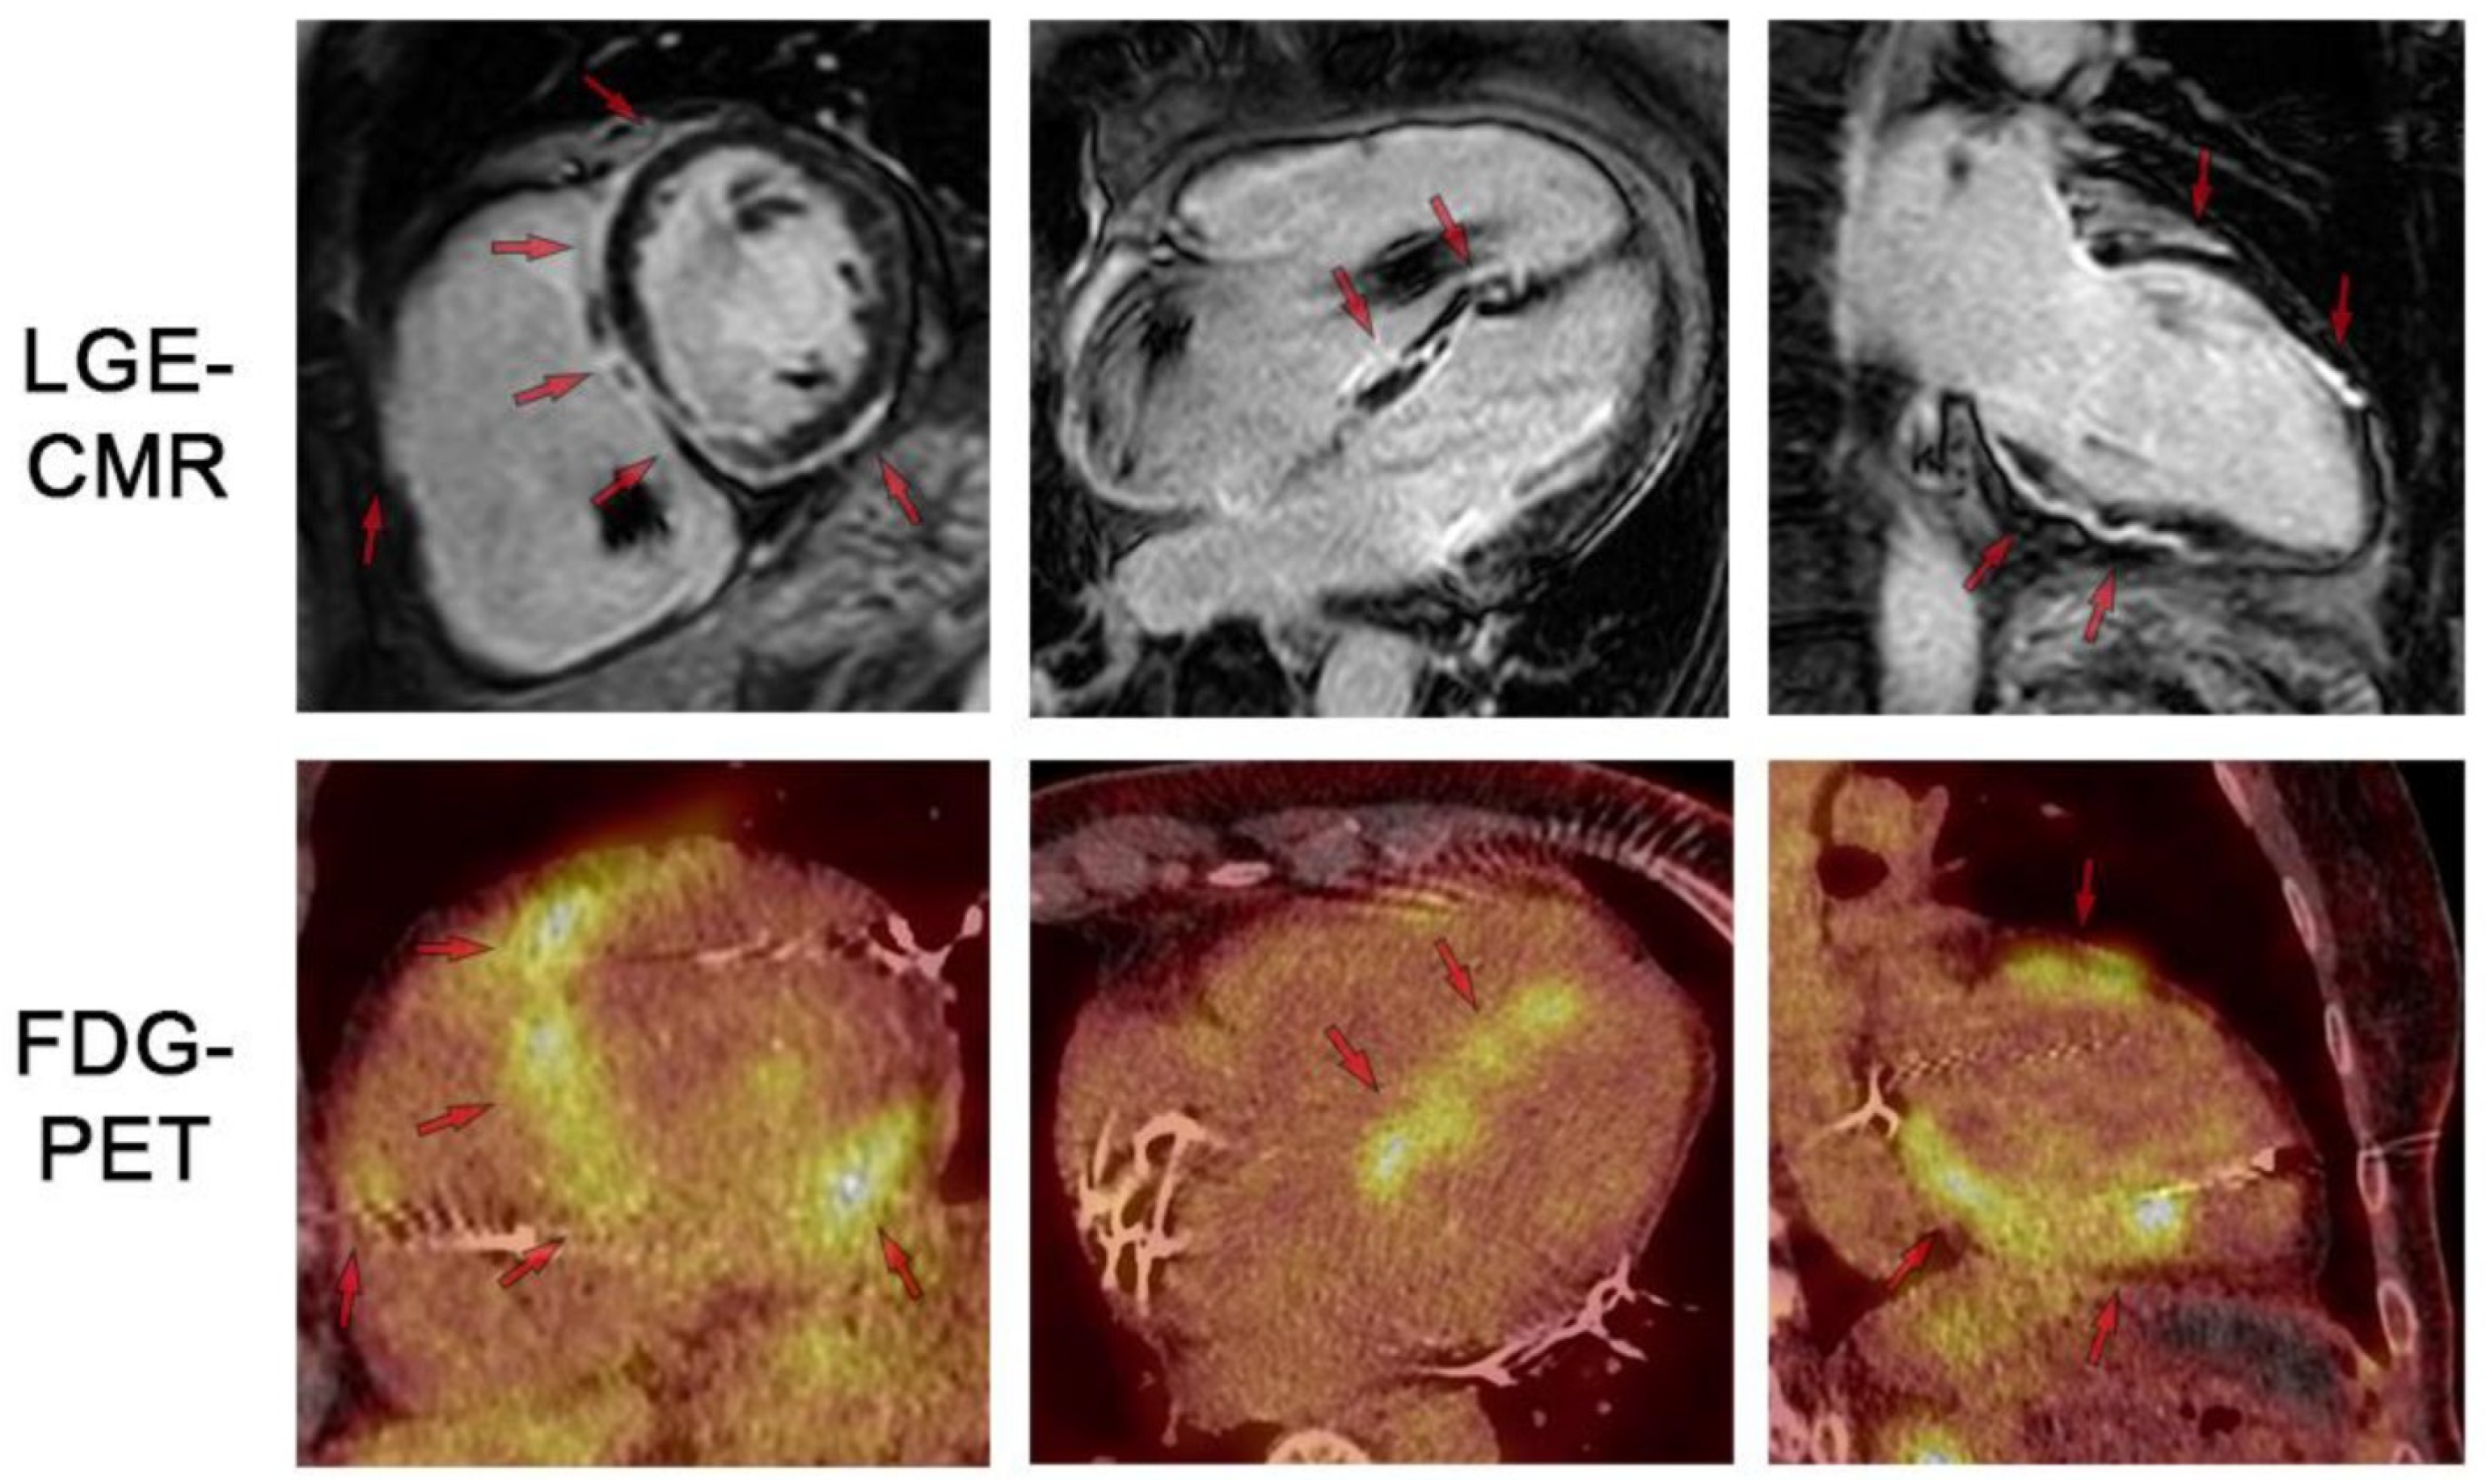

Figure 9.

LGE-CMR and FDG-PET images for respective short-axis, 4-chamber, and 2-chamber orientations. Top row shows LGE-CMR fibrosis imaging. Arrows indicate areas of abnormal LGE in a patchy distribution pattern reflecting inflammation and/or scar. Bottom row shows fusion FDG-PET/CT showing patchy uptake in regions of scar, suggesting active inflammation. Note the artifact in the RV cavum caused by the ICD lead. LGE: late gadolinium enhancement. FDG: 18-fluordesoxyglucose positron emission tomography. Reproduced from: Korthals,. D, et al. (2024) [12]. Licensed under CC BY 4.0 (https://creativecommons.org/licenses/by/4.0/ accessed on 15 December 2025).

- LGE Pattern: The most common pattern is mid-myocardial or subepicardial LGE in the basal and mid-anteroseptal and -inferoseptal segments. A highly specific finding is the “hook sign,” where LGE extends from the septum into the right ventricular insertion point [52]. Transmural LGE can also occur, mimicking myocardial infarction.

- Mapping: Active inflammation shows elevated native T1 and T2 values in affected segments. ECV is also elevated [53].

- Functional Abnormalities: RWMAs corresponding to LGE locations, LV dilation, and reduced EF are common.

- Multimodality Imaging: 18F-FDG PET/CT is often used alongside CMR to identify active granulomatous inflammation, especially when CMR shows LGE but it is unclear if it represents active disease or fibrosis [54].